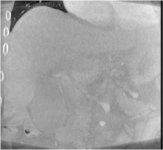

An example of CT/CBCT and MR/CBCT registration results are shown in figures 3 and 4, respectively. For both cases, the CBCT image (first column) was acquired intra-operatively after needle insertions and was employed as a reference for image registration. The pre-operative image is displayed before registration (second column), after PM-EA (third column) and after PM-EA+Evo (fourth column). The occurrence of patch shifts is reported for each spatial direction in panels (m–o): for each histogram, the shift with maximal occurrence is shown by the red dashed line. For panels (a–l), a ROI — manually defined on the CBCT image/encompassing the liver — is shown using red dash lines. Our visualization shows an improved correspondence of the contour of the liver with the manually defined liver boundary when the PM-EA solution is employed (see 3(c,g,k) and 4(c,g,k)). Moreover, an even better correspondence of the contour is observable using the PM-EA+Evo solution (see 3(d,h,l) and 4(d,h,l)).

Trans.

[X-Y]

CBCT

(a)

MRI / No registration

(b)

MRI / PM-EA

(c)

MRI / PM-EA+Evo

(d)

Sag.

[X-Z]

(e)

(f)

(g)

(h)

Cor.

[Y-Z]

(i)

(j)

(k)

(l)

(m)

(n)

(o)